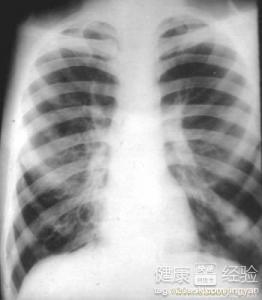

支氣管炎是一種常見的呼吸系統(tǒng)疾病,其癥狀包括咳嗽、咳痰、呼吸急促等,許多患者關心的問題是:支氣管炎能自愈嗎?本文將詳細解析支氣管炎的類型、癥狀、治療方法以及能否自愈的問題,幫助患者更好地了解并應對這一疾病。

支氣管炎是指氣管、支氣管黏膜及其周圍組織的炎癥,根據其發(fā)病的急緩,可分為急性支氣管炎和慢性支氣管炎,急性支氣管炎通常由于病毒、細菌等感染引起,癥狀明顯且病程較短;而慢性支氣管炎則由于長期吸煙、空氣污染等因素導致,癥狀持續(xù)較長時間,易反復發(fā)作。

支氣管炎的典型癥狀包括咳嗽、咳痰、呼吸急促等,部分患者可能伴有發(fā)熱、胸悶等癥狀,咳嗽通常為首發(fā)癥狀,隨著病情的發(fā)展,逐漸出現咳痰,痰量可能因病情嚴重程度而異,在嚴重的情況下,患者可能出現呼吸困難、喘息等癥狀。